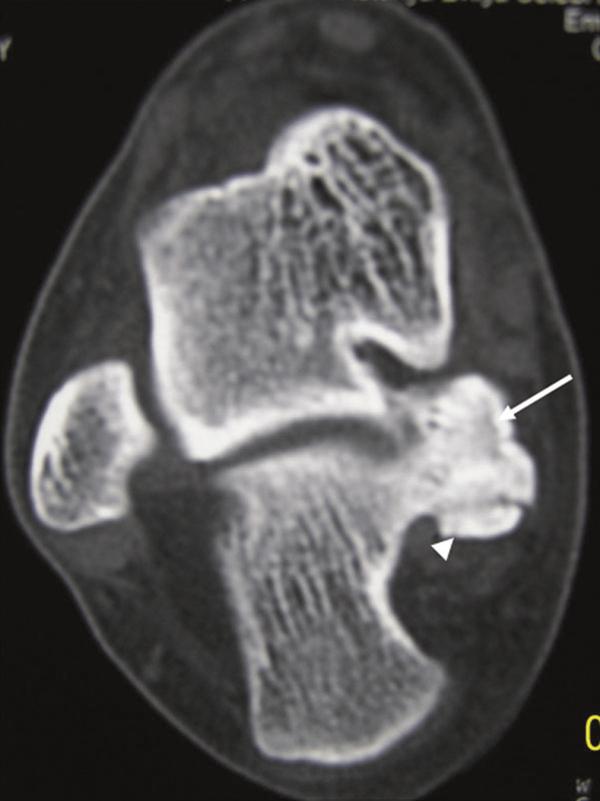

We report the clinical and radiologic findings of a calcaneal osteochondroma with an extremely rare placement and painfull, rapid reccurence following surgical excision in a skeletally mature female. The lesion showed growth the first-operation later and was re-operated. Histopathological examination did not show malignancy.

我们报告了一名骨骼成熟女性跟骨骨软骨瘤的临床和影像学表现,该肿瘤位置极其罕见,手术切除后疼痛且迅速复发。病变在首次手术后出现生长并再次接受手术。组织病理学检查未显示恶性。